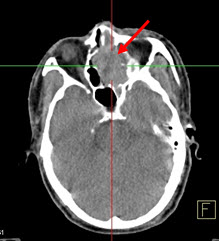

Hình 2. Bệnh nhân Trần V. V., nam, 57 tuổi. Chẩn đoán: u lympho hốc mũi; Giải phẫu bệnh: WF5. Hình CT, PET và PET/CT cho thấy tổn thương u ở vùng hốc mũi trái (mũi tên) tăng hấp thu FDG.